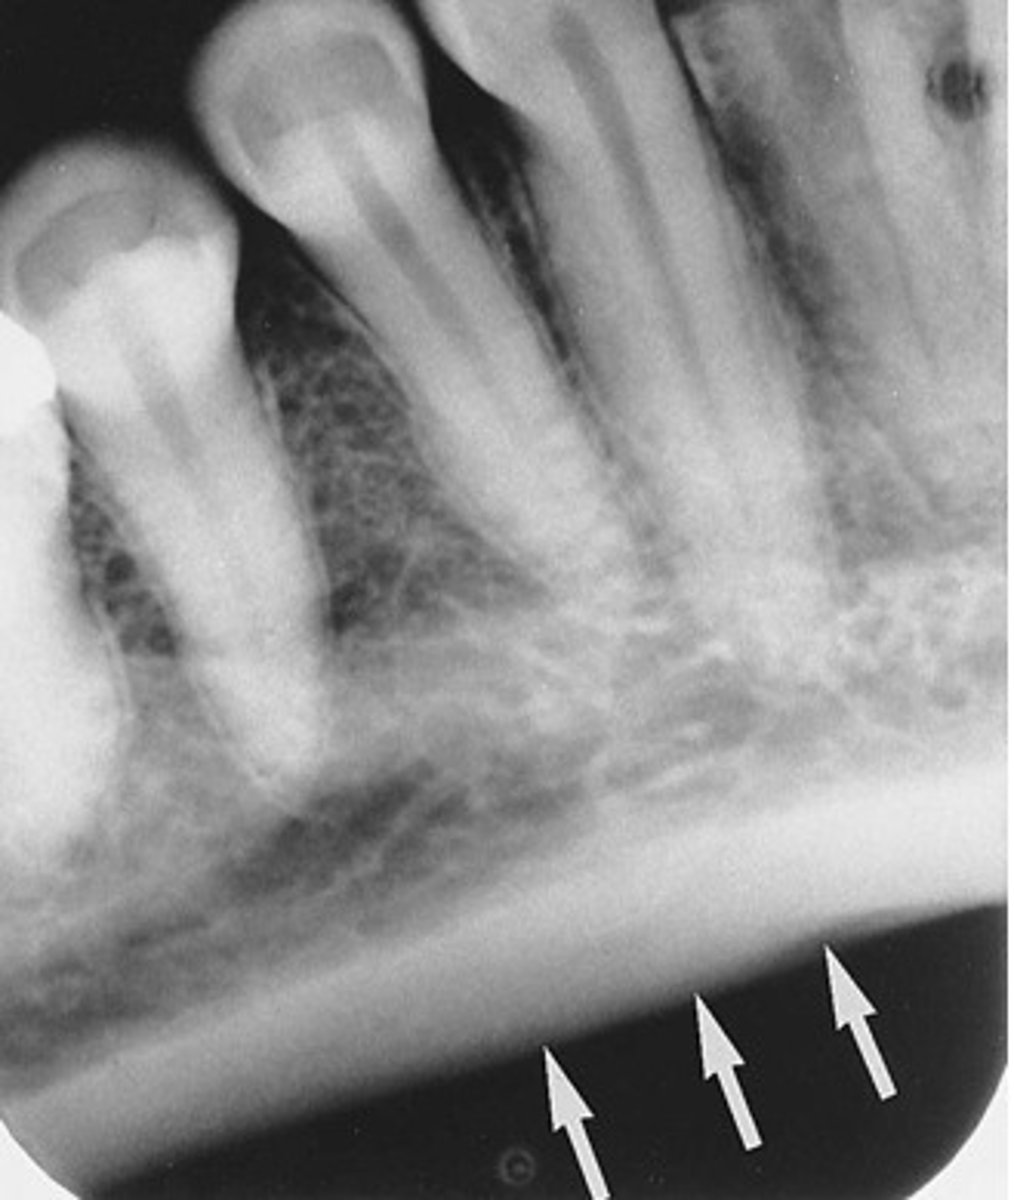

Mandibular canal

What is the radiolucent structure seen here?